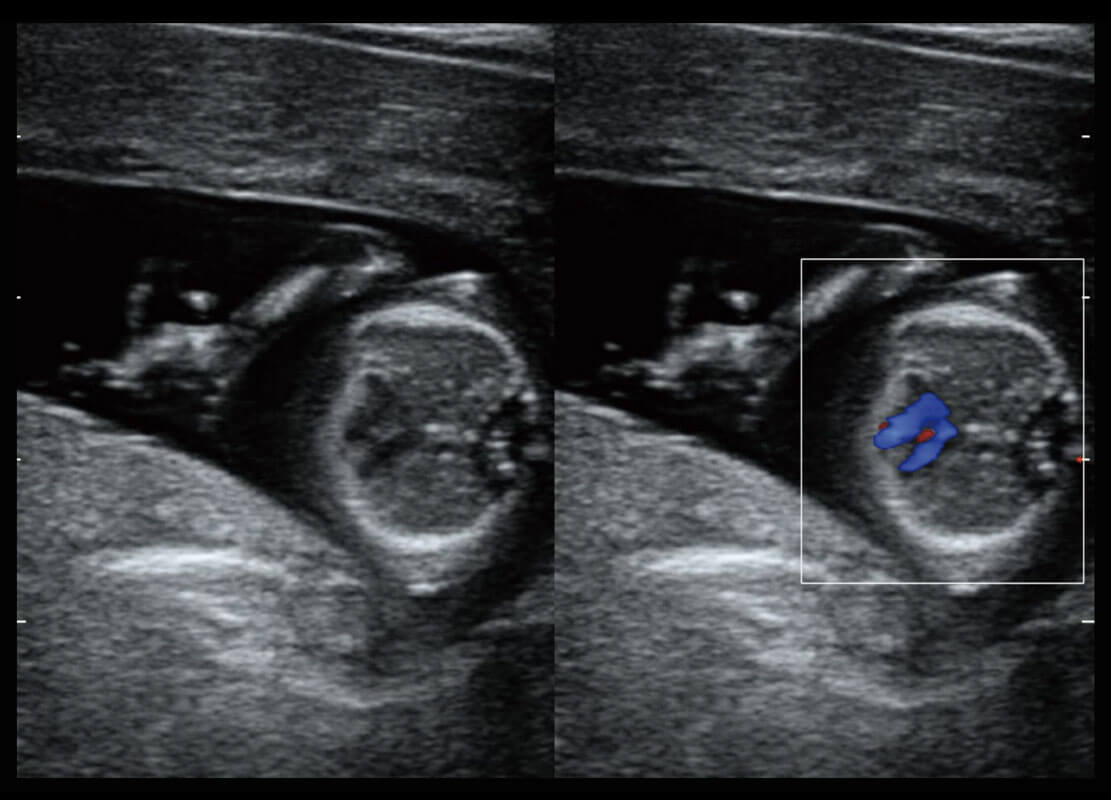

早孕-胎心

高分辨率容积成像-早孕胎儿

胎儿体循环

光影成像-孕囊

P60在胎儿早孕期超声筛查中为您带来优异的图像质量。